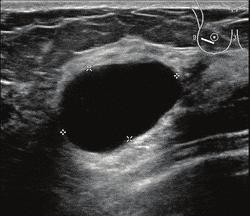

Ik besloot eerst maar eens een ruime maand te wachten. Deze cystes kunnen vanzelf ook weer verdwijnen. Maar niet in mijn geval dus. Nou heb ik echt een heel leuke huisarts waarmee ik kan lezen en schrijven en ik belde haar toch voor overleg. Na wat wikken en wegen besloten we maar te gaan voor een echo op de mammapoli. In juni heb ik nog een mammografie gehad i.h.k.v. het bevolkingsonderzoek. Een echo is sowieso minder heftig en een cyste laat zich daar goed herkennen.

Tijdens de echo telden we uiteindelijk wel 12 cystes dus ik ben ruim voorzien voorlopig. Pas als ze 2 à 3 cm zijn kun je ze zelf voelen. Antwoord op mijn hamvraag kreeg ik helaas niet: moet ik nou bij elke nieuwe knobbel weer de mallemolen in? Of mag ik vertrouwen op het bevolkingsonderzoek (immers loop ik niet méér risico op borstkanker dan andere vrouwen)? Zelf zoeken op internet leverde werkelijk geen antwoord op deze vraag en ook de radioloog kon, mocht of wilde hier geen zinnig antwoord op geven.